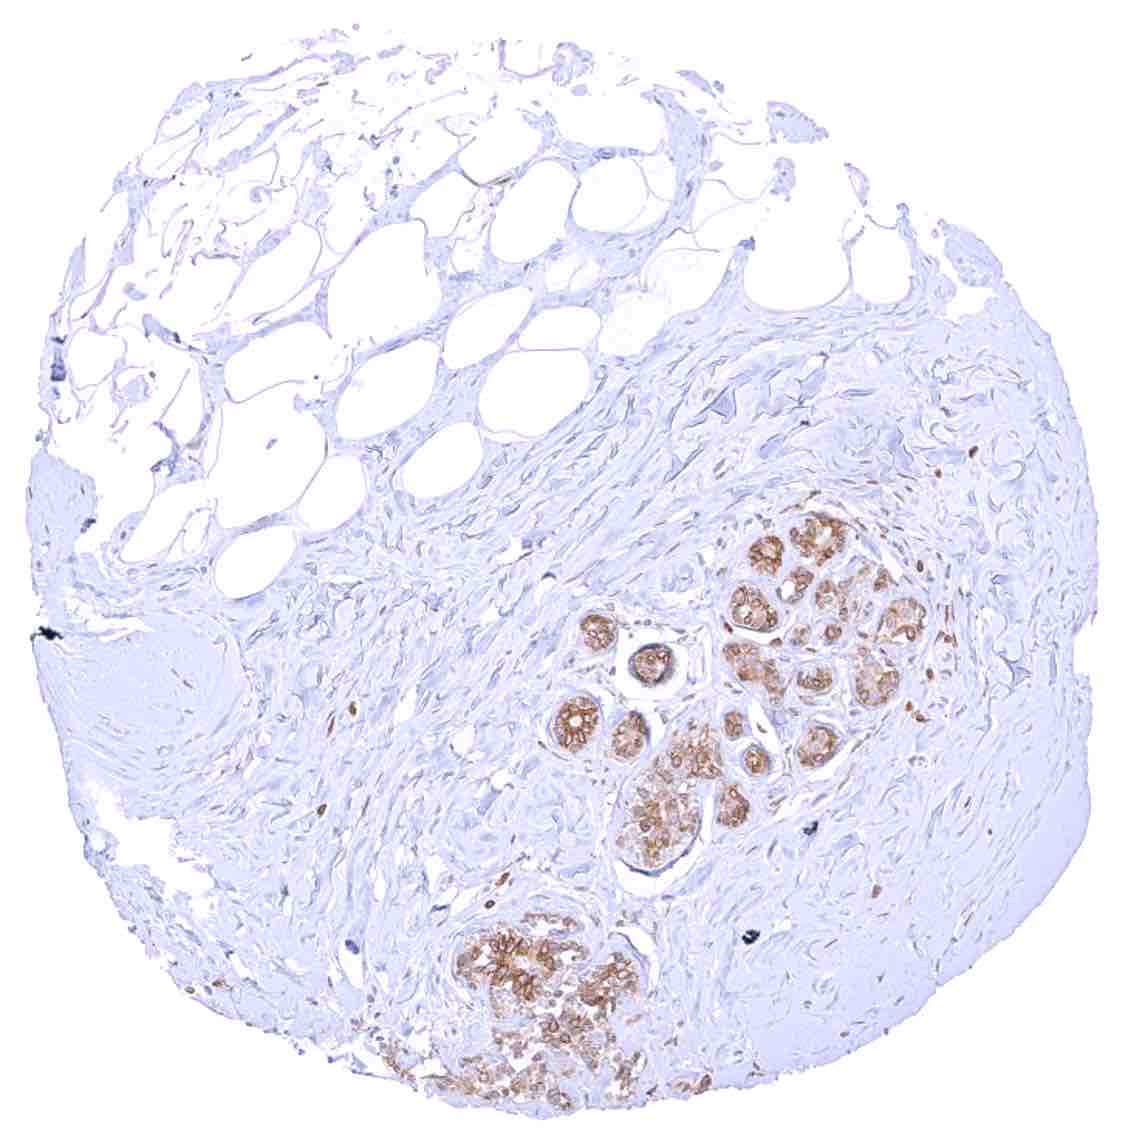

| Female genital | Breast | Distinct cytoplasmic bcl-2 staining of epithelial cells (acinar cells stain stronger than myoepithelial cells). |